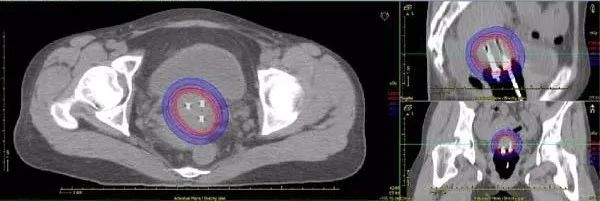

(2)组织间插值治疗(照射)Interstitial (irradiation):

放射源经手术植入肿瘤组织内;可以是一时性也可以是永久性植入。

③ 通常做成粒状源,用于高、低剂量率的临时性或永久性插值治疗;

④ 用于插值的优点:插值体积外剂量下降很快;可用薄于200μm厚的铅作屏蔽保护正常组织;大量减少了不必要的照射;

⑤ 与铱-192源相比的缺点:需特定设备制备粒源,花费较多人力;价格较高;剂量分布明显地依赖于被插值组织的结构。